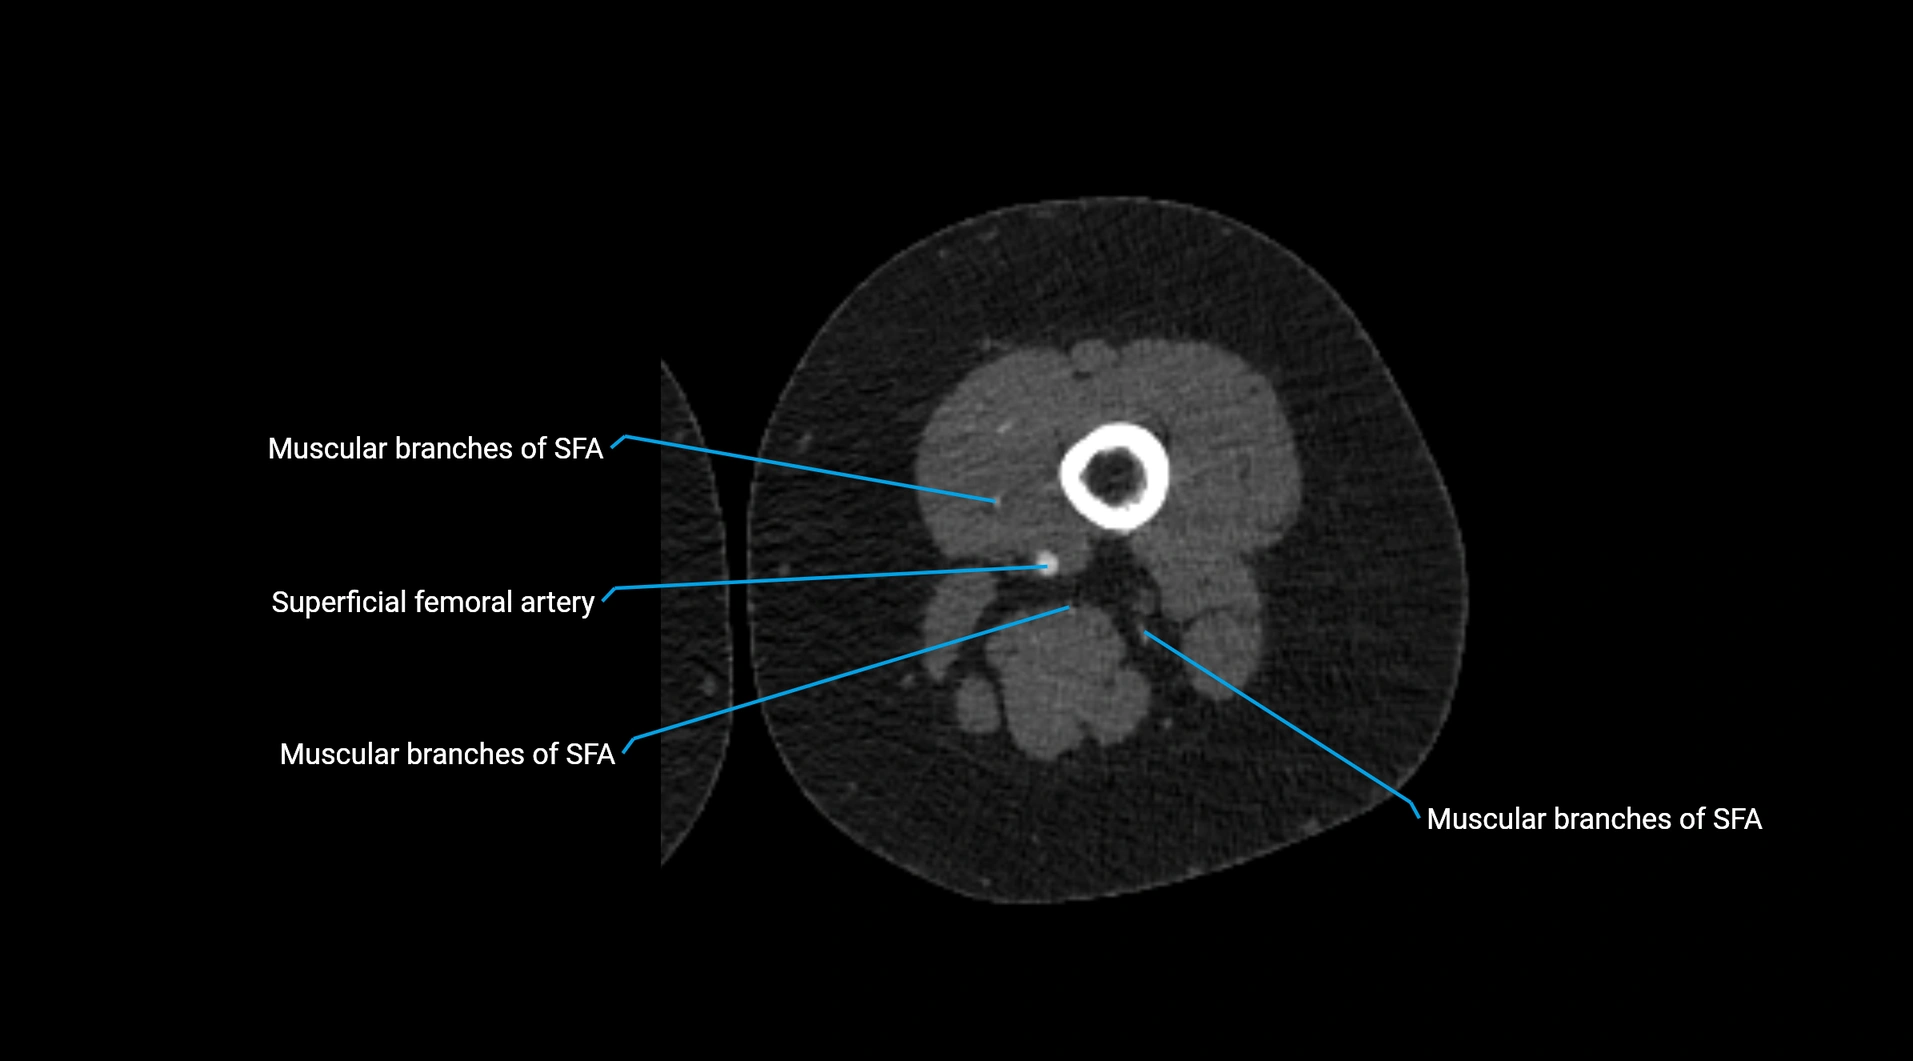

Contrast-enhanced CT (CTA):

• Gold standard for abdominal aortic imaging

• Provides excellent detail of lumen, wall, aneurysm, thrombus, and branch vessels

• Multiplanar and 3D reconstructions help in aneurysm measurement, stent graft planning, and dissection evaluation

• Detects acute rupture, traumatic injury, or occlusion with high sensitivity